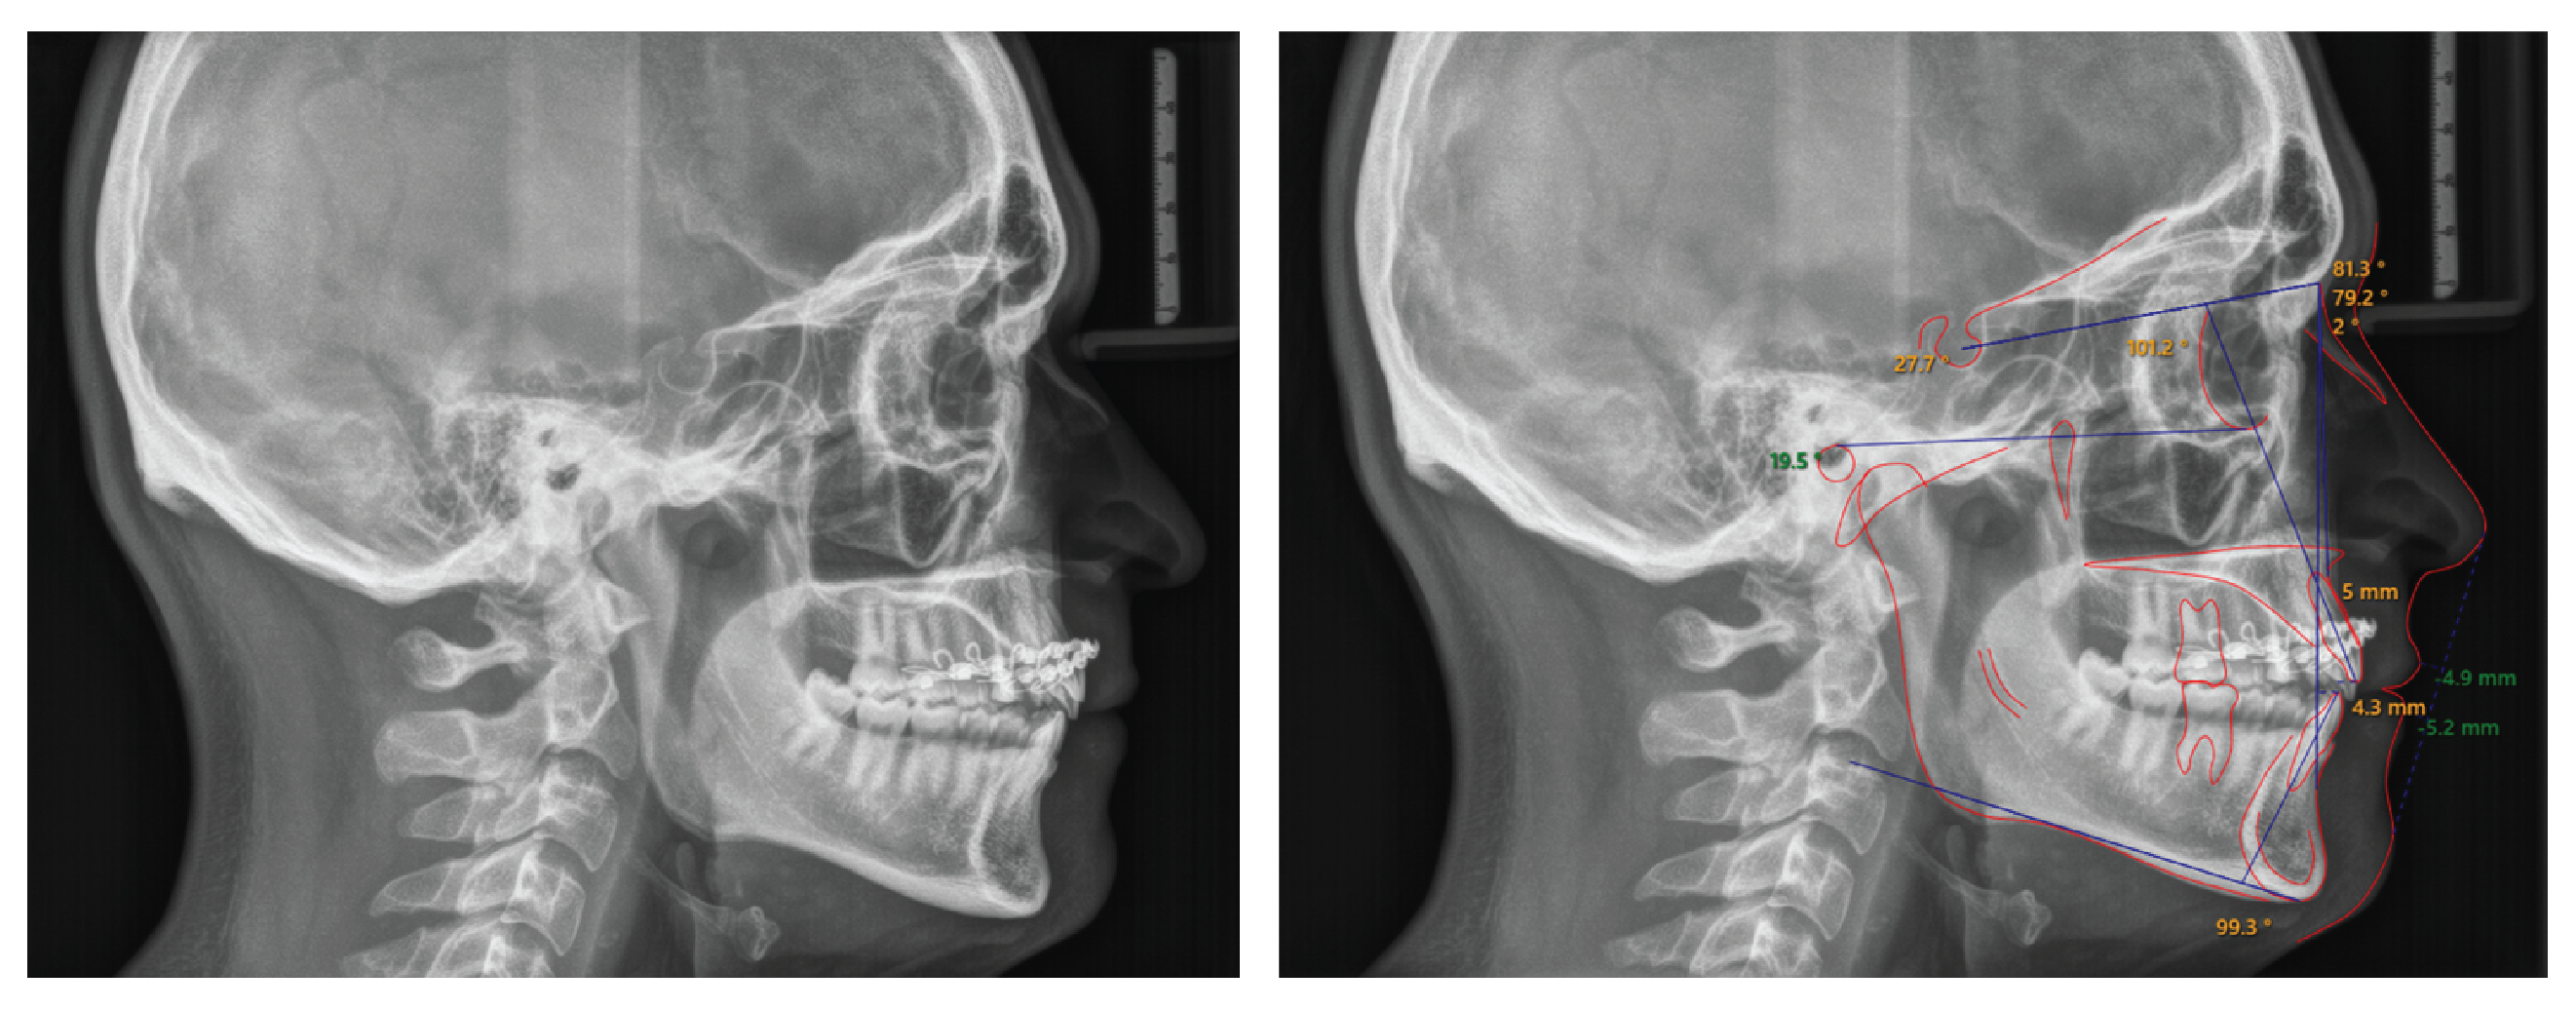

The panoramic radiograph (Figure 3) revealed a complete dentition except for the maxillary third molars, which had been previously extracted. The roots of all teeth were fully developed, but there were signs of blunting on the maxillary left central and a fracture at the tip of the apex on the maxillary lateral incisor. Remodeling of the condyles was also observed. Lateral cephalometric analysis (Figure 4 and Table I) revealed a skeletal Class I relation (ANB= 2°) with a hypo-divergent mandible (FMA = 19.5°). The inclinations of the maxillary and mandibular incisors were within normal limits, with U1°- SN measuring 101.2° and IMPA measuring 99.3°, respectively). Soft tissue analysis indicated that the distances from the upper and lower lips to the E-line were deficient, measuring -4.9 mm and -5.2 mm, respectively.

Figure 4: Pre-treatment lateral cephalometric radiograph and analysis. Pre-treatment lateral cephalometric radiograph shows a skeletal Class I jaw relation (ANB is 2°), hypo-divergent mandible (FMA is 19.5°), and upper and lower incisor inclination within normal limits. Soft tissue analysis indicates that the distances from the maxillary and mandibular lips to the E-line were increased, suggesting lip retrusion.